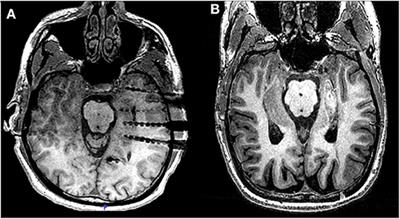

Emotional Recognition in Patients With Mesial Temporal Epilepsy Associated With Enlarged Amygdala